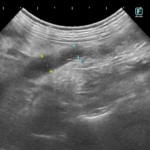

パピヨンの尿管結石症例に対し、外科的に結石摘出を実施した。摘出結石の分析により、成分はシリカ(ケイ酸、SiO₂)と同定された。シリカ結石は犬の尿石症の中でも発生頻度が極めて低いとされ、特に上部尿路(尿管)での発生報告は限られている。また、本結石は溶解療法が無効であり、尿管閉塞を伴う症例では外科的摘出、尿管ステント、SUBシステムなどの介入が必要となる。本症例ではCTやエコーなどの画像診断により尿管閉塞を確認し、腎機能温存を目的として外科的摘出を選択した。術後経過は良好で、現在は再発予防として飲水管理(低ミネラル水)および食事内容の調整を中心に経過観察を行っている。シリカ結石は飲水中の溶存ケイ酸量や生活環境との関連が示唆されており、まれな結石であり、成分分析に基づく原因評価と長期管理戦略が重要であると考えられた。